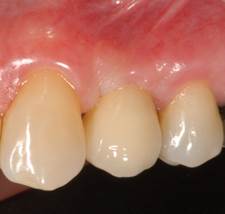

- Pacientes que buscan un resultado especialmente estético en la región anterior

- La encía alrededor de las restauraciones sobre estos implantes siempre tiene un aspecto absolutamente saludable sin signos de inflamación